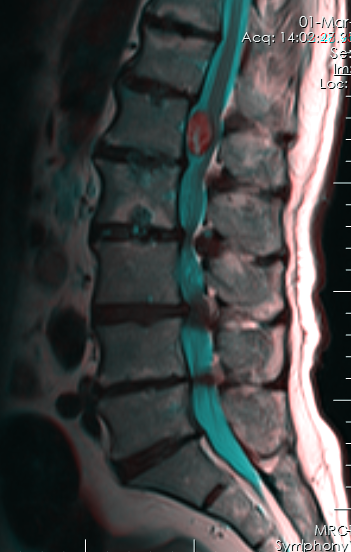

Mηνιγγίωμα θωρακικής μοίρας της σπονδυλικής στήλης με σημαντική πίεση στον νωτιαίο μυελό. |